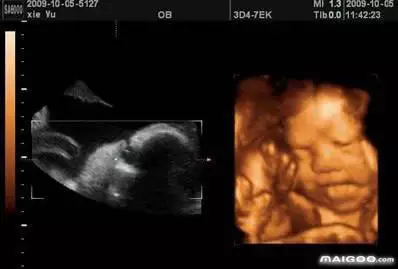

女孩和男孩都一样,四维超声同其它超声检查相比,可以实时观察人体内部的动态运动,也能准确地分辨出胎儿的性别。虽然四维彩超能够看清胎儿的性别,但在检查过程中,为了避免透露胎儿的性别,医生会主动的回避胎儿的性别特征以及下半身

四维彩色超声诊断仪是目前世界上***的彩色超声设备,很多准爸妈做了四维彩超之后,都会习惯性的问医生“宝宝是男是女?”虽然四维彩超能够看清胎儿的性别,但在检查过程中,为了避免透露胎儿的性别,医生会主动的回避胎儿的性别特征以及下半身,同时,在后期制作光盘时,也会将可能泄露宝宝性别的部分进行处理。所以说,四维彩超是可以检测到宝宝的性别,但需要提醒准爸妈的是,透漏胎儿性别按照**规定非医学目的分辩胎儿男女是的,所以正规的医院是不会通过任何途径告诉、暗示胎儿性别的。其实,无论是男孩或是女孩都是夫妻爱情的结晶,准爸妈们更应该关心胎儿是否健康、发育是否正常等因素,而不是在乎性别与否。四维单子3秒钟看男是女。

一般来讲,做四维的**时间是孕中期的22-26周。因为这个时间段,量适中,胎儿的主要身体躯干和身体已经基本成型,做出的图像比较清晰,可以很方便医生观察孩子各方面的发育情况,有利于医生摸清孩子的身体状况,对宝宝的进行全方位的检查。可以看看宝宝的唇部,脊柱、大脑、肾脏、骨骼等方面的发育情况进行排畸筛查。